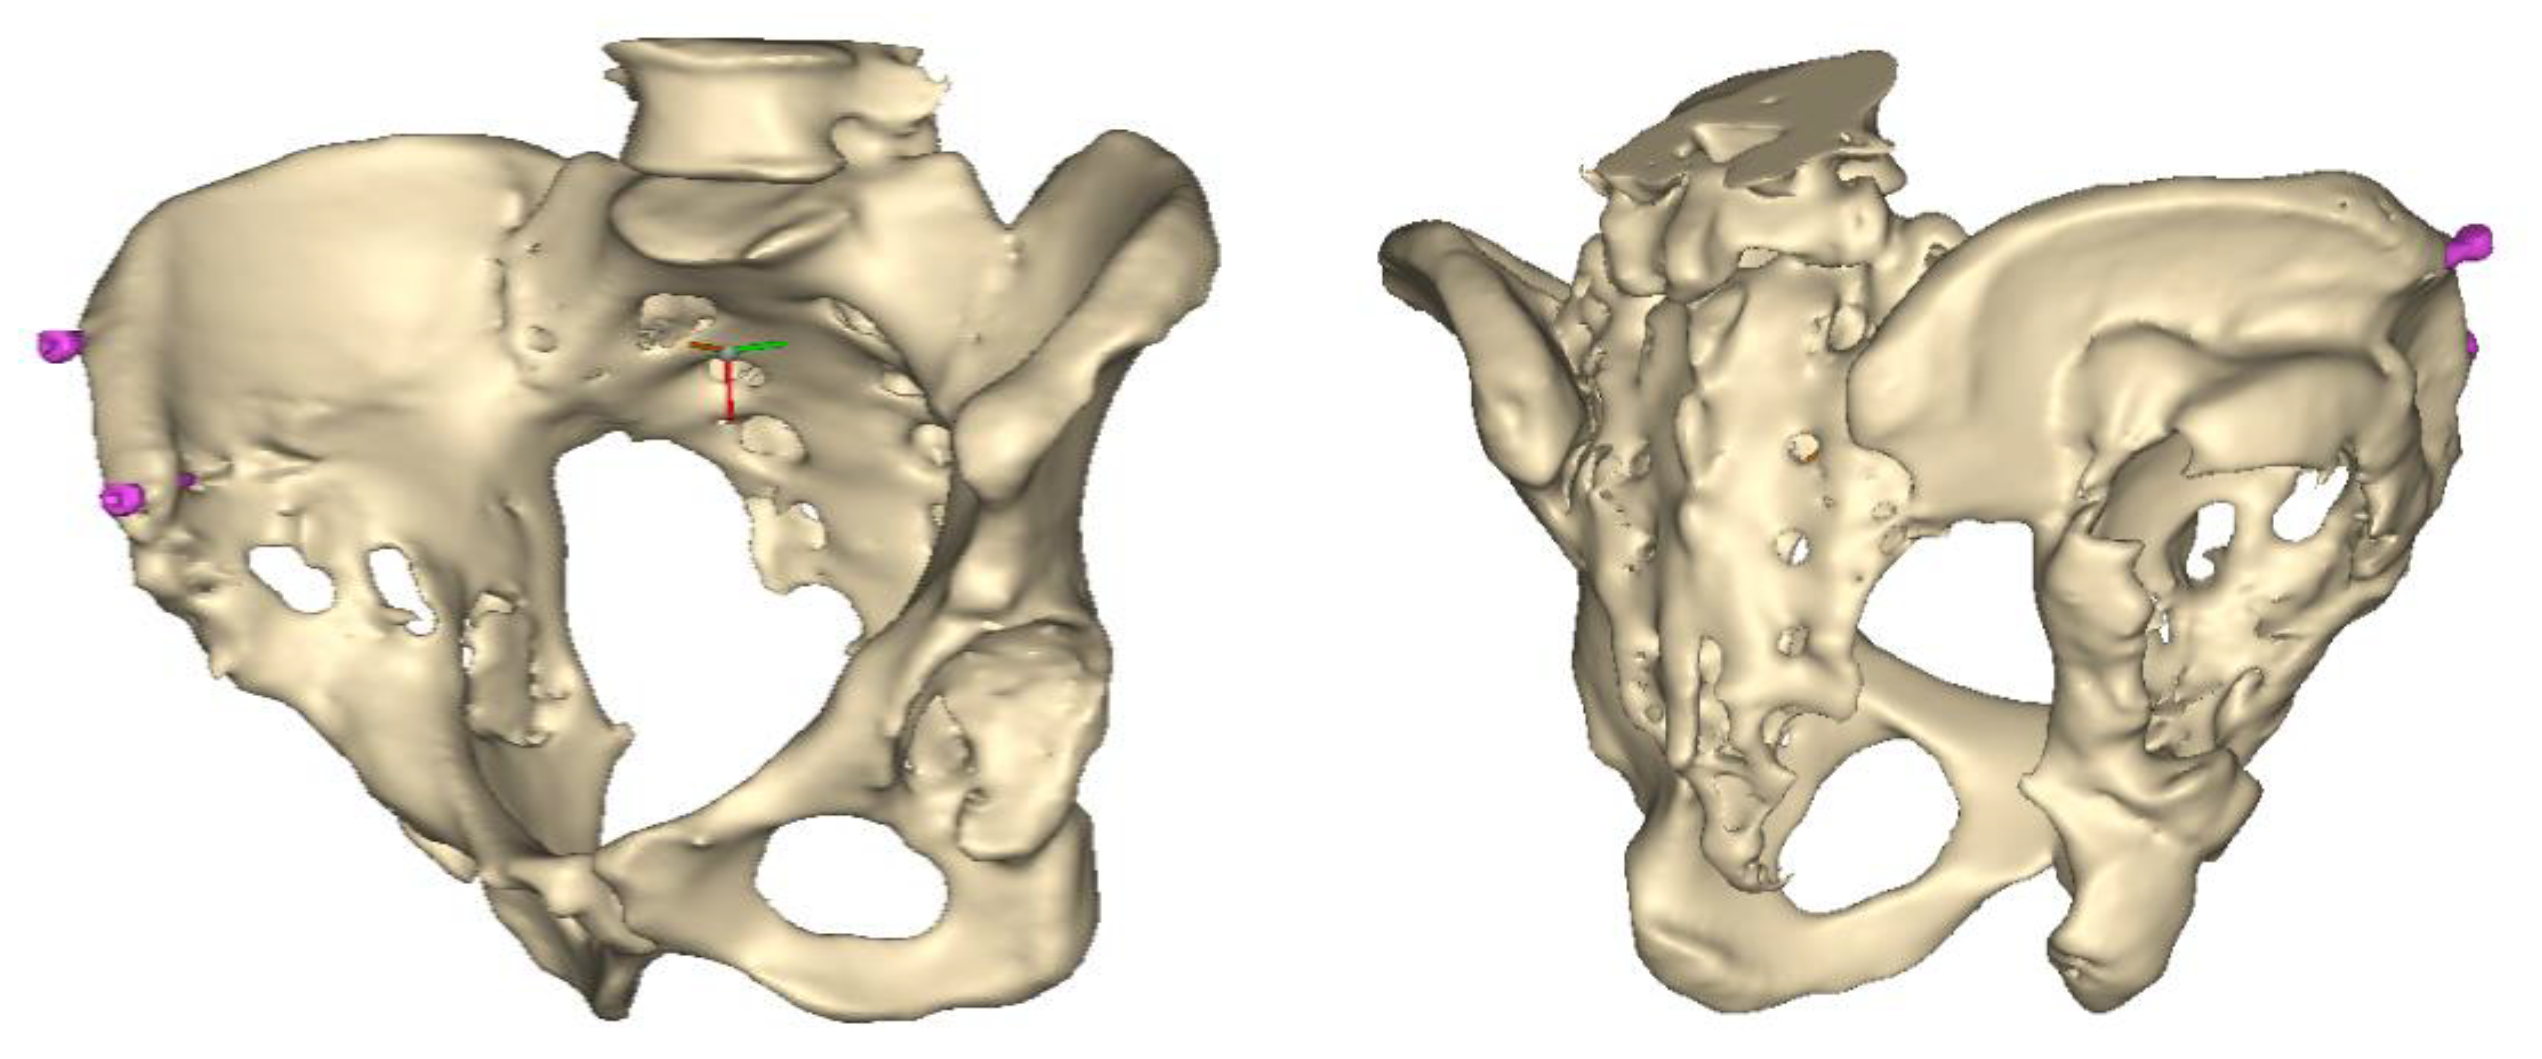

Figure 2.

Design steps of the aiming device: (a) Stemmed acetabular cup with guiding wire; (b) drawing of the guiding sleeve and the reference points; (c) connection of the reference points and the guiding sleeve; and (d) adjustment of the handle.

Next, the aiming device was designed, starting with the guiding sleeve. Its length was typically 60–70 mm, which provides appropriate guidance. However, this length is influenced by the position of the femur, which can be seen in the 3D reconstruction. Even with a diameter of 10–12 mm, the guide wire is safely targeted (Figure 2b). A chamfer of 1–2 mm around the inlet surface of the guide cylinder ensures that no cutting edge is formed at the boundaries of the surfaces. On the outlet side, also chamfered, was left 2–3 mm from the bone surface, thus avoiding the possibility of the guide stem accidentally resting on the surface of the shaft, thus altering the aiming direction. In the early versions, the targeting body adopted the unique shape of the damaged side of the hip, with a groove for the index finger to help hold it in position. In practice, however, it proved difficult to drill and hold the finger in a safe position at the same time. Furthermore, it was found to be problematic when the targeting device was in contact with the bone over a large surface area. The accuracy of the 3D reconstruction and the preparation of the hip may have had a negative effect on the direction of the targeting device in the event of large surface contact and, thus, the accuracy of aiming. These observations led to further development. Later practice was to position the target with three reliable bony sections. Once the support points were designated, slots were constructed between the designated points and the central part of the device. A hexagonal and a triangular socket was constructed to replace the finger positioning. A stainless-steel hand tool was used to retain it in position. However, the hand tool that was used limited the space available for the drilling tool, making it difficult to use the targeting device.

Our previous practice was to use three reliable bony formations to position the aiming device, but experience has shown that these can break off during surgery. However, in addition to two titanium screws, a third point on the lower bony frame provided a secure three-point fixation. For the ideal adjustment of its position, the support arms ending in 12 mm diameter spheres wrapped around the head of the two reference screws, and the third one touched a reliably solid part of the lower edge of the bony acetabulum. The edited spheres, using a Boolean subtraction operation, take the shape of the selected periacetabular bony anatomical point on the anterior margin of the defective acetabulum and the screw heads. Grooves were created in the spheres for the screw heads, considering the need to be able to remove the targeting device after drilling while keeping the guiding wire in position.

These three reference points were linked to each other and to the guide sleeve by means of suitably designed connecting profiles. It was considered that these reference points would be deep and difficult to reach during the operation, so the aiming cylinder of the guiding wire and the spheres around were connected by means of half-toroids of 50–60 mm diameter, considering bypassing the soft tissue (Figure 2c). In the last, fourth version, to replace the hexagonal and triangular sockets, a handle was added to the aiming device outside the skin surface (Figure 2d).